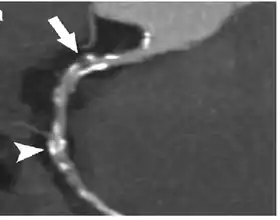

Coronary Computed Tomography Angiography (CCTA)

Computed tomography angiography (CTA), an imaging methodology using a ring-shaped machine with an X-ray source spinning around the circular path so as to bathe the inner circle with a uniform and known X-ray density. Cardiology uses are growing with the incredible developments in CT technology. Currently, multidetector CT, specially the 64 detector-CT are allowing to make cardiac studies in just a few seconds (less than 10 seconds, depending on the equipment and protocol used). These images are reconstructed using algorithms and software.

Gated Cardiac CT (CCT)

Cardiac CT (CCT) is a modified form of the traditional chest CT due to the difficulty of imaging the complex, moving heart.[16] This is achieved through the use of thin slices and high-resolution scanning, as well as the addition of electrocardiogram (ECG) gating or triggering to capture a motion-free image. Standard CT scans are acquired in either Axial or Helical modes, while CCT adds the ECG gating dimension to these modes to capture images of the heart.[16] These modifications are necessary to obtain the required data from the planar slice images, which are reconstructed from back-projected transmitted data obtained by radial excursion of the X-ray tube and detector.[16]